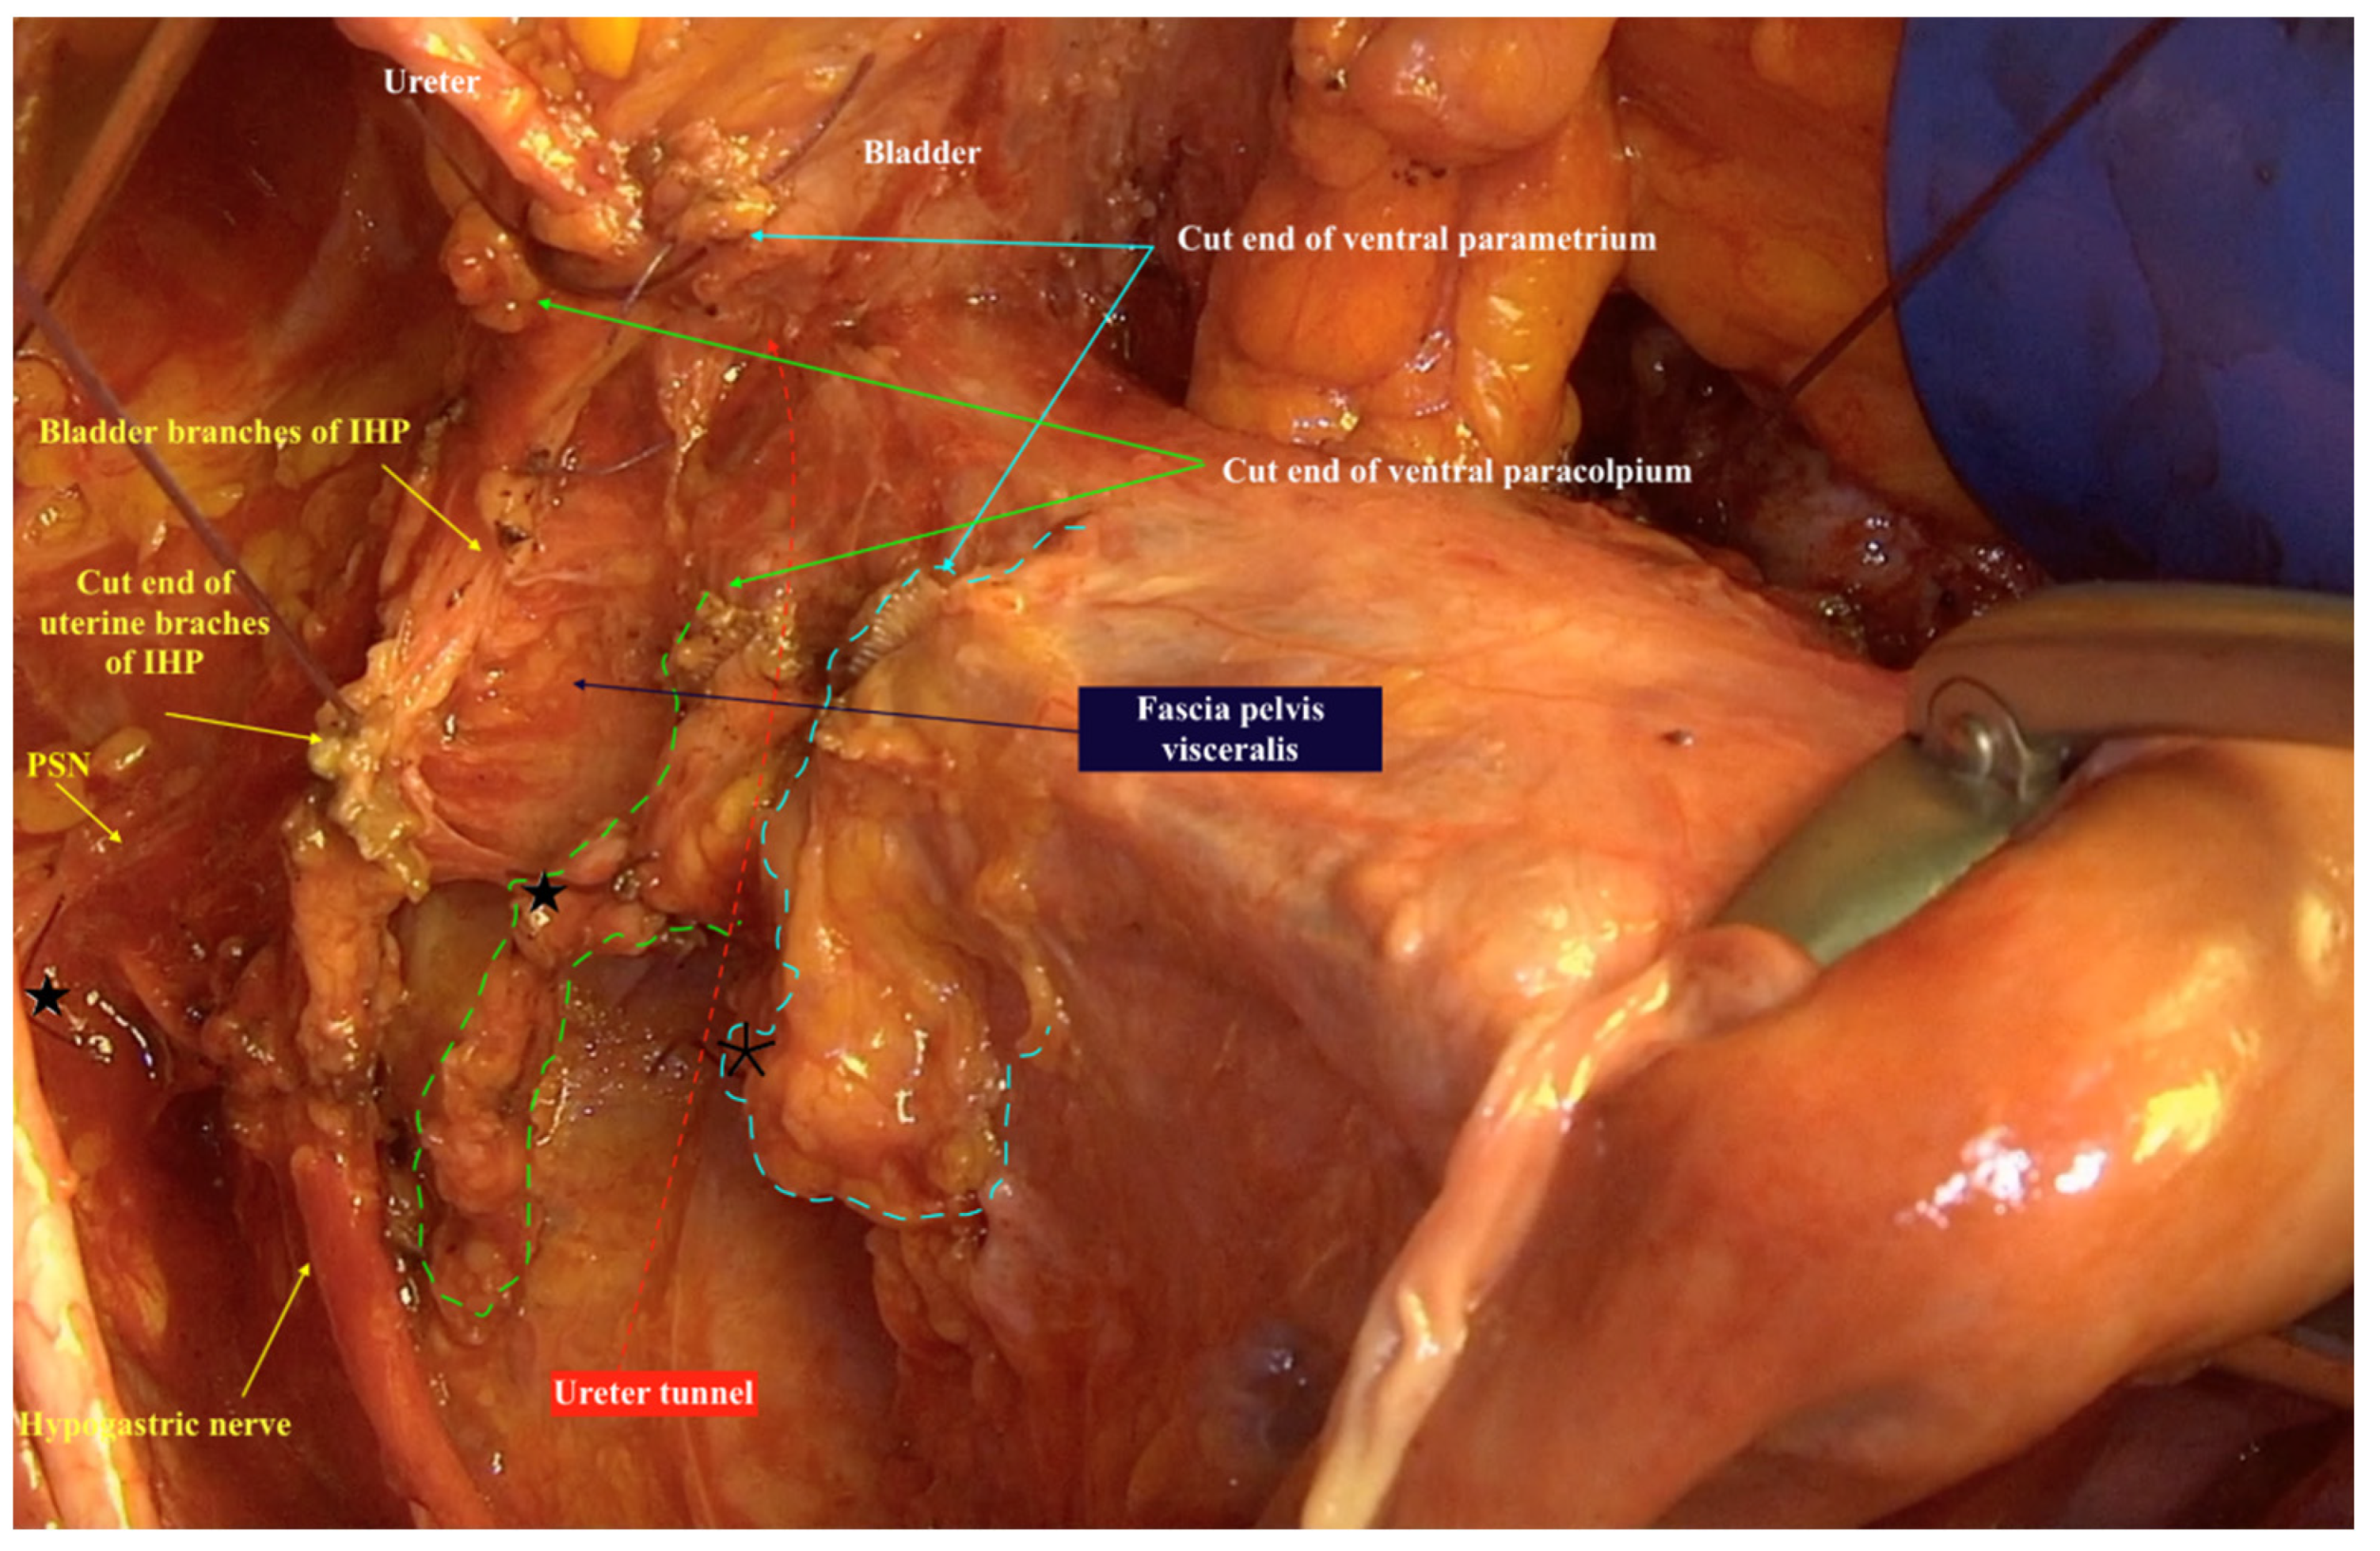

The three-dimensional anatomic template for the resection of parametrium and paracolpium depends on the precise anatomy of parametrium and paracolpium published before [9,10] and bases on the central position of the cervix and upper vaginal in the concept of radical hysterectomy and on the ureter as a stable anatomic landmark, which splits these tissues (Paracervix) to parametrium (above = cranial and craniomedial from the ureter) and paracolpium (beneath = caudal and caudolateral from the ureter, Figure 2).

Figure 2.

The resected three-dimensional parametrium above the ureter/ureter tunnel and the resected three-dimensional paracolpium beneath the ureter/ureter tunnel in type IV Muallem classification of radical hysterectomy. The spared left hypogastric nerve, left inferior hypogastric plexus and their branches to the bladder are even good to be seen lateral from the specimen. Parametrium marked with a dotted blue line, paracolpium marked with a dotted green line, ureter tunnel marked with a dotted red line. ★ cut end of vaginal vessels (wrongly known as deep uterine vein), * cut end of uterine vessels, IHP: inferior hypogastric plexus, PSN: pelvic splanchnic nerves.

In this way, every part of the three-dimentional parametrium and paracolpium has a proximal aspect (at the cervix in the case of parametrium and at the vaginal wall in the case of paracolpium) and a distal aspect (at the bladder trigone in case of ventral parametrium and ventral paracolpium, at the internal iliac vessels in the case of lateral parametrium and lateral paracolpium, and at the rectum sidewall and sacrum in case of dorsal parametrium and dorsal paracolpium). Figure 3 shows the three-dimensional parametrium in a cross-section of the midpelvis, and Figure 4 shows the three-dimensional paracolpium in a cross-section directly above the pelvic floor.